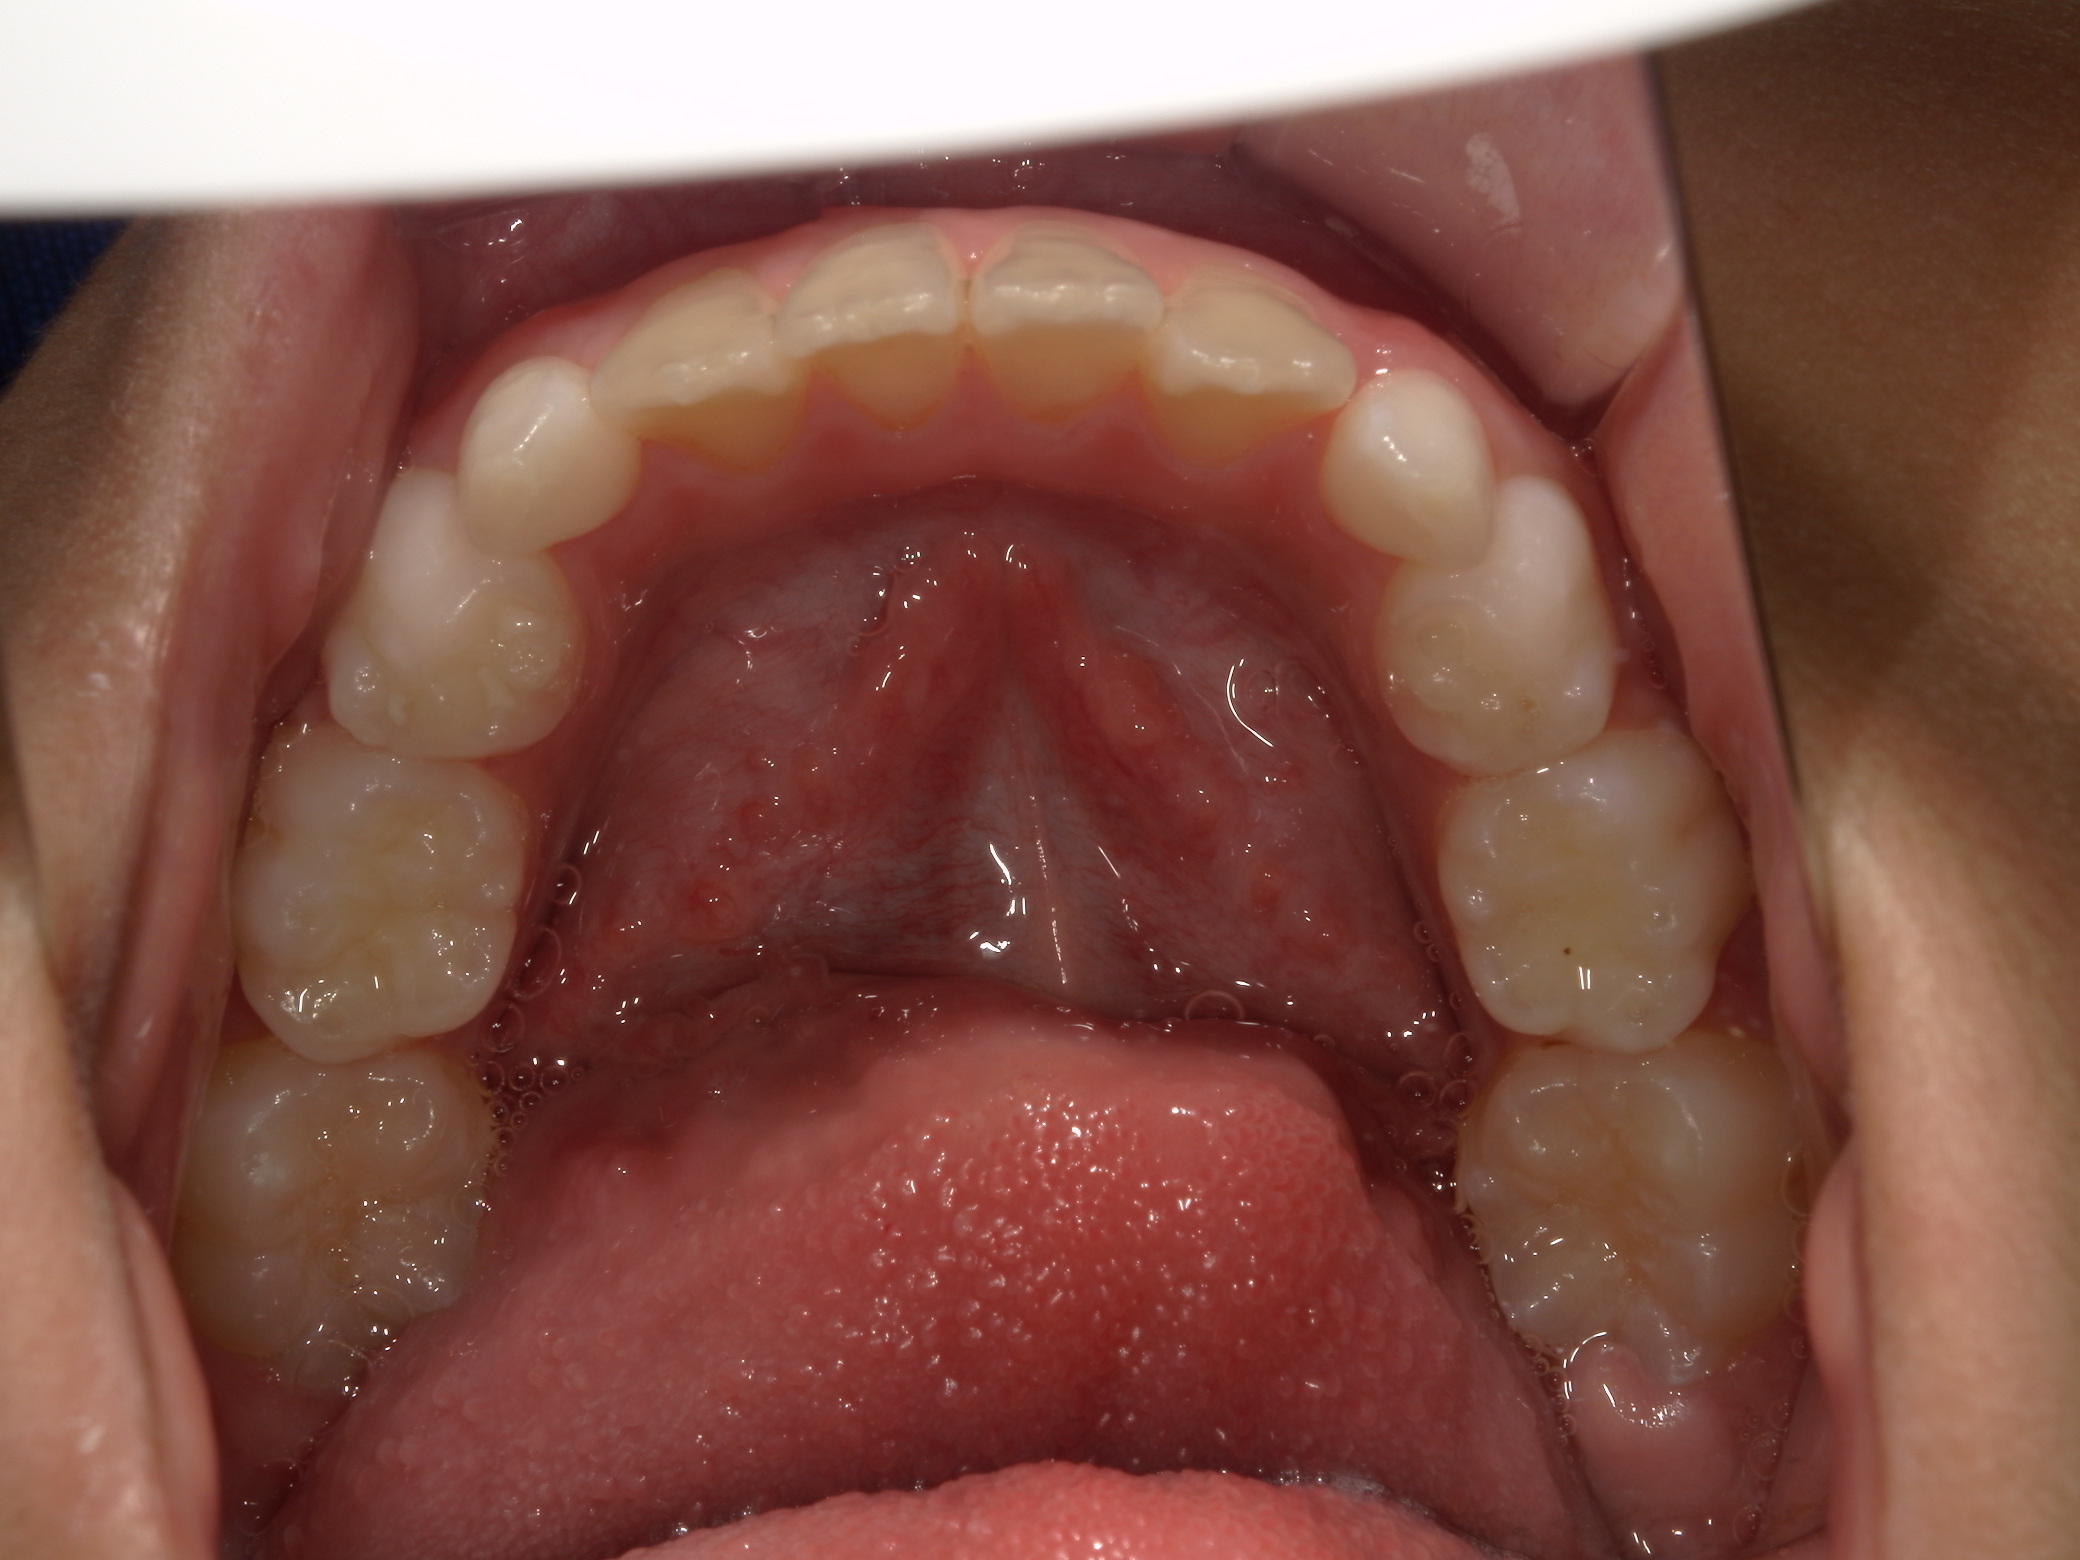

| 年齢・性別 | 8歳9ヶ月の女児 |

|---|---|

| 主訴 | 歯並びの乱れを気にされて来院された患者様です。将来的なスペース不足と歯のねじれ(翼状捻転)が懸念されました。 |

| 治療期間・回数 | 2年10ヶ月・19回 |

| 費用 | 430,000円(税別) |